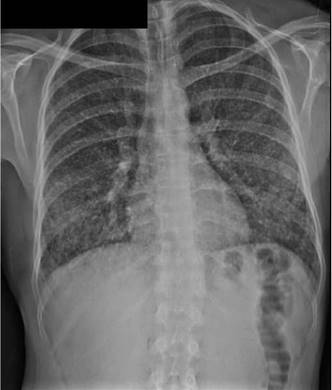

En la radiografía inicial de tórax se evidenciaron infiltrados miliares difusos (figura 3). Ante estos hallazgos, se sospechó un cuadro de tuberculosis pulmonar y se ordenó baciloscopia seriada del lavado broncoalveolar. No se encontraron bacilos ácidoalcohol resistentes. El cultivo para micobacterias y la prueba de reacción en cadena de la polimerasa, realizada con el equipo GeneXpert, fueron negativos.

En el segundo caso, se sospechó inicialmente tuberculosis dada la sintomatología y los resultados de imagenología. Las fallas en la anamnesis inicial no permitieron hacer el diagnóstico presuntivo de esta micosis, pero en una segunda valoración, se sospechó histoplasmosis pulmonar epidémica por el antecedente de haber ingresado a una cueva de murciélagos. Por ser un paciente sin ningún tipo de inmunocompromiso y por el tratamiento empírico antimicótico administrado, se pudo tratar la enfermedad.

La histoplasmosis tiene dos formas de manifestarse, tanto clínica como radiológicamente. La primera es como una enfermedad pulmonar aguda o epidémica que se acompaña de lesiones neumónicas segmentarias, a menudo grandes, que tienden a curar y se designan como lesiones tempranas. La segunda forma suele presentarse como una complicación de la primera; es una enfermedad crónica caracterizada por cavitación persistente y aumento de la fibrosis pulmonar, y a menudo, por insuficiencia pulmonar progresiva; esta forma se puede confundir con tuberculosis pulmonar 6,22,23.